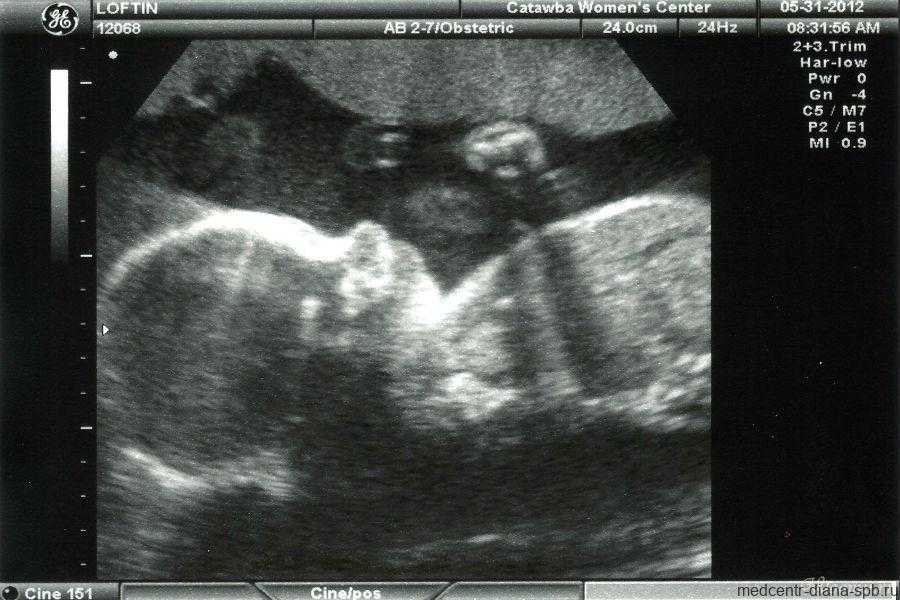

При классическом виде УЗИ на монитор выводится плоская картинка — проекция внутренних органов на плоскость. 3Д УЗИ даёт объёмное изображение, а 4Д УЗИ позволяет продемонстрировать видео — в реальном времени можно увидеть все движения ребёнка, рассмотреть его черты лица, оценить его состояние.

4Д УЗИ позволяет увидеть не плоское изображение малыша, а объёмное видео

Этот вид УЗИ в гинекологии – диагностический метод, посредством которого определяется состояние плода, выявляются аномалии в формировании и развитии органов и систем, появляется возможность проанализировать параметры плода в трехмерной проекции (длина, высота, глубина). Результат исследования можно получить сразу после процедуры.

Ультразвуковое исследование в формате 3D и 4D – это диагностика беременности с использованием ультразвуковой терапии, основанная на эхолокации. Суть метода: отражение ультразвуковой волны от тканей и органов, улавливаемое датчиком. Благодаря такому новому и современному оборудованию получается очень качественное изображение.

Исследования позволяют в подробностях рассмотреть внутренние органы и анатомические параметры плода, выявить любую патологию, осуществить допплеровское картирование сосудов, которое необходимо при пренатальном обследовании.

3D УЗИ

УЗИ 3Д плода позволяет получить объемное цветное изображение, в деталях рассмотреть все органы и системы ребенка еще во время беременности. Можно сделать запись на CD диск всех важнейших моментов формирования и развития Вашего малыша в трехмерном пространстве.

Это обследование по сути ничем не отличается от уже привычного, традиционного УЗИ. Оно совершается при помощи проникающего сквозь ткани и по-разному в них распространяющегося ультразвука, где все зависит от плотности исследуемой среды и от ее состава. Однако если на классическом обследовании ультразвук дает картину, которую никто, кроме профессионала, не сможет понять.

Только после указаний врача родители смогут разглядеть крупные косточки плода или, к примеру, позвоночник. В случае же 3д процедуры получается совсем другое изображение. Перед родителями предстает объемное изображение, больше похожее на обычную фотографию, но высочайшего качества и высокого разрешения. С помощью этой процедуры можно даже рассмотреть лицо малыша и посчитать все пальцы.